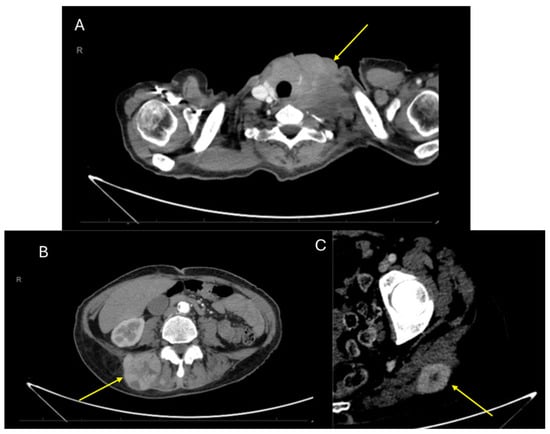

| 5 [our case] | 58/F | Left neck/4 cm | Positive: S100, SOX10, CD99 (weak/focal), Fli-1, and synaptophysin (focal). Negative: Melan-A, HMB-45, CKIT, AE1/AE3 | EWSR1 gene translocation | Surgery (radical resection) and radiotherapy | Yes: 48 mo | Yes: 36 mo | Died: 54 mo |